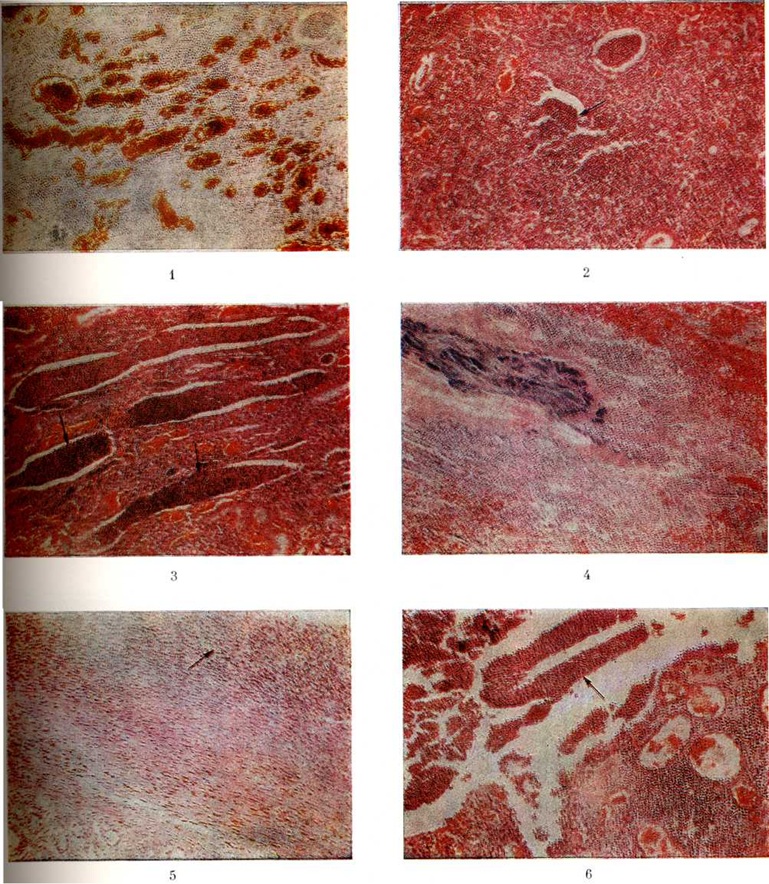

При остром серозном Пиелонефрит отмечается отёк стромы мозгового и коркового вещества, полнокровие микроциркуляторного русла (цветной рисунок 1), дистрофически-некробиотические изменения эпителия проксимальных и дистальных канальцев, дилатация их просвета. В зонах максимальных тубулоэпителиальных поражений в составе стромального экссудата имеется примесь полиморфноядерных лейкоцитов. Клубочки остаются интактными.

При очаговом гнойном Пиелонефрит наблюдаются перитубулярные или интратубулярные скопления полиморфноядерных лейкоцитов, клеточного детрита и гомогенных белковых масс в пределах нескольких нефронов (цветной рисунок 2 и 3). При диффузном гнойном Пиелонефрит может отмечаться разрушение стенок канальцев (тубулорексис), а иногда и капсулы клубочков (инвазивный гломерулит) с образованием мочевых затёков.

В просвете расширенных канальцев видны белково-лейкоцитарные цилиндры и колонии микробов (цветной рисунок 4). Прогрессирование гнойного воспаления может завершиться апостематозным нефритом, изолированным абсцессом или карбункулом почки, представляющим обширные участки сливающихся гнойников и очагов некроза. Карбункул почки нередко осложняется гнойным паранефритом (цветной рисунок 5). У больных декомпенсированным сахарным диабетом Пиелонефрит может осложниться некрозом сосочков пирамид (смотри полный свод знаний Почечных сосочков некроз).

В чашечках и лоханках при гнойном уриногенном Пиелонефрит наблюдается полнокровие сосудов, гнойная инфильтрация их стенок, эрозивно-язвенные дефекты, дистрофия и десквамация эпителия, лимфангииты и флебиты субэпителиальных отделов (цветной рисунок 6). Гнойное воспаление распространяется преимущественно по лимфатических, и венозным коллекторам стромы отдельных пирамид и в меньшей степени по просвету дистальных канальцев и собирательных трубок.